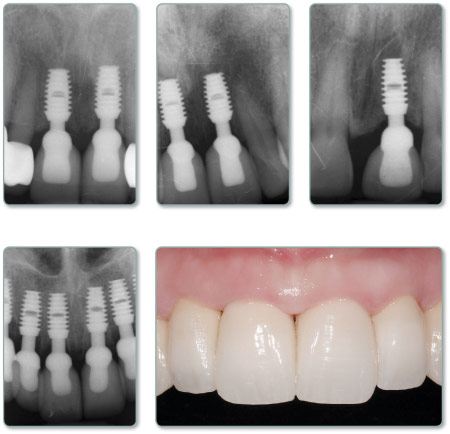

El sistema Bicon Permite al dentista ofrecer restauraciones funcionales y estéticas a los pacientes, para que realmente puedan disfrutar de las prótesis de implantes que se ven y se sienten como los dientes naturales . Además, se evitan los olores y sabores asociados con tornillos.

El IMPLANTE BICON fue diseñado para restaurar la dentición sin utilizar tornillos. Por esta razón , los médicos , técnicos, y los pacientes no experimentan las limitaciones y frustraciones inherentes al uso de tornillos.